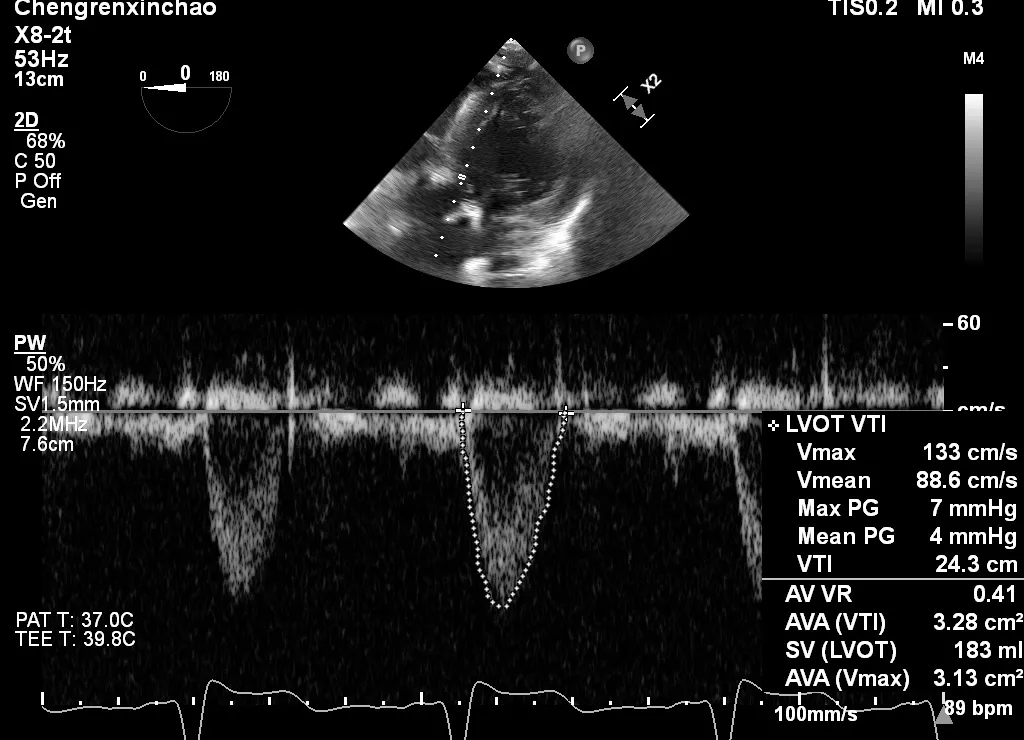

术后超声

术后心脏超声示:主动脉瓣生物瓣置换术后,人工生物瓣膜最大流速1.33m/s,平均压差4mmHg,连续性方程估测瓣膜开口面积3.13cm2。人工瓣微量反流,主动脉根部及升主动脉增宽,左心肥大。

术后主动脉瓣瓣口面积3.13cm2

(连续性方程估测)